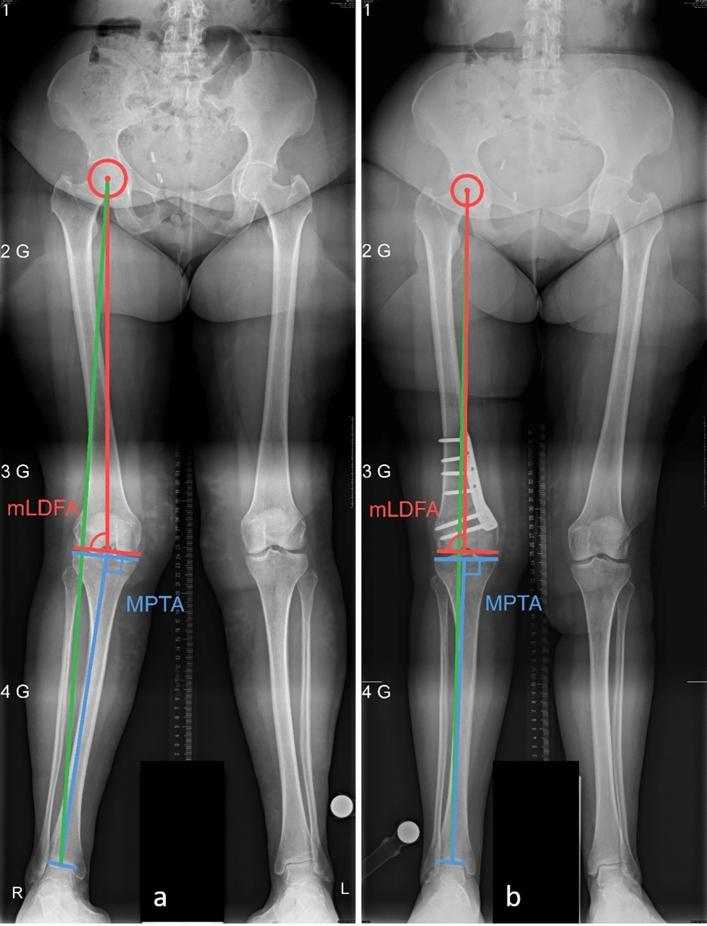

RESULTS

The median (range) age was 47 (17-63) years, height 1.68 (1.56-1.98) m, body mass 80 (49-105) kg, and body mass index (BMI) 27.4 (18.6-37.0) kg/m. The clinical follow-up was 21 (7-81) months, the need for total or unicompartmental knee arthroplasty (TKA/UKA) and hardware removal was followed up for 59 (7-108) months postoperatively. Preoperatively, hip-knee-ankle angle (HKA, negative values denote varus) was 7.0 (2.0-13.0)°, mechanical lateral distal femoral angle (mLDFA) was 83.7 (79.9-88.2)°, and mechanical proximal tibial angle (MPTA) was 89.0 (86.6-94.5)°. Postoperatively, HKA was -1.3 (-9.0-1.2)° and mLDFA was 90.8 (87.3-97.3)°. The incidence of minor and major complications was 25% and 14%, the incidence of delayed and nonunion was 18% and 4%, respectively. At the last follow-up, 18% of the patients had pain at rest, 25% during activities of daily living, and 39% during physical activity, and 71% were satisfied with the outcome. 7% of the cases received a TKA/UKA, 71% received a hardware removal.

中位(范围)年龄为 47(17-63)岁,身高 1.68(1.56-1.98)m,体重 80(49-105)kg,体重指数(BMI)27.4(18.6-37.0)kg/m。临床随访时间为 21(7-81)个月,全膝关节置换术(TKA)/单髁膝关节置换术(UKA)和内固定取出的需要时间为术后 59(7-108)个月。术前髋膝踝角(HKA,负值表示外翻)为 7.0(2.0-13.0)°,机械外侧股骨远端角(mLDFA)为 83.7(79.9-88.2)°,机械胫骨近端角(MPTA)为 89.0(86.6-94.5)°。术后 HKA 为-1.3(-9.0-1.2)°,mLDFA 为 90.8(87.3-97.3)°。轻微和严重并发症的发生率分别为 25%和 14%,延迟愈合和不愈合的发生率分别为 18%和 4%。末次随访时,18%的患者有静息痛,25%的患者在日常生活中有疼痛,39%的患者在体力活动中有疼痛,71%的患者对结果满意。7%的患者接受了 TKA/UKA,71%的患者接受了内固定取出。